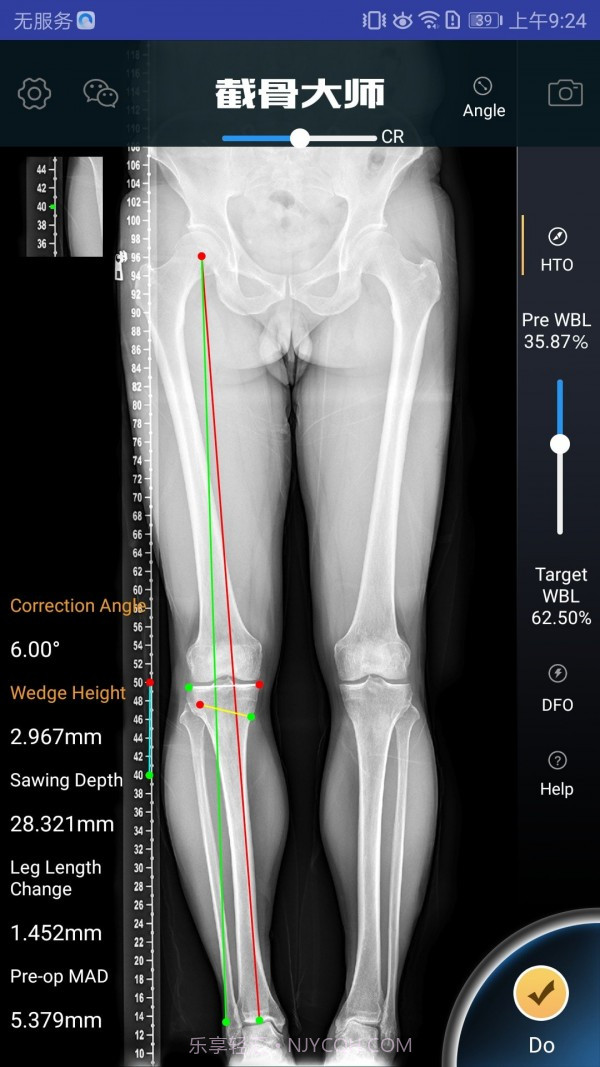

我感觉截骨大师真的是个宝藏APP,特别适合骨科医生和医疗人员使用呢。它的手术模拟功能超级高效,能让医生在手术前清晰地了解手术效果,避免在实际操作中出现失误。而且,它的参数计算非常精准,真的是为医生的工作提供了很大的帮助。用这款软件,你不仅能节省大量准备时间,还能显著提高手术的成功率,对患者的治疗也有很大保障。作为医生,这款工具简直是必不可少的选择!

高效的手术模拟功能,医生可以直观了解手术效果

精准的参数计算

精准的算法支持,确保每个计算结果都可靠